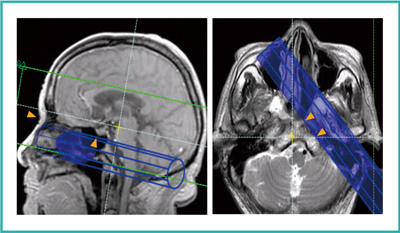

BeamSatの設定位置

目的血管を選択的に抑制するためには,それ以外の血管を抑制しないようにBeamSatの設定位置が重要になる。健常ボランティアにおいて,片側のICAのみを選択的に抑制できるBeamSatの位置を検討した。検討の結果,サジタル断面では鼻根部とトルコ鞍に接する位置に設定し,アキシャル断面では錐体-斜台に接する位置に設定することで(図4),椎骨(VA)-脳底動脈(BA)や中大脳動脈(MCA)など,目的以外の血管の抑制を防げることがわかった。

図4 BeamSatの設定(左ICA岩様部抑制)

SAG断面:鼻根部とトルコ鞍に接する位置

AX断面:錐体-斜台に接する位置

BeamSat専用UI:BeamSatの表示は,実線部分が位置決め画像より手前側,破線部分が奥側,ハッチング部分がBeamSatと位置決め画像の交面である。